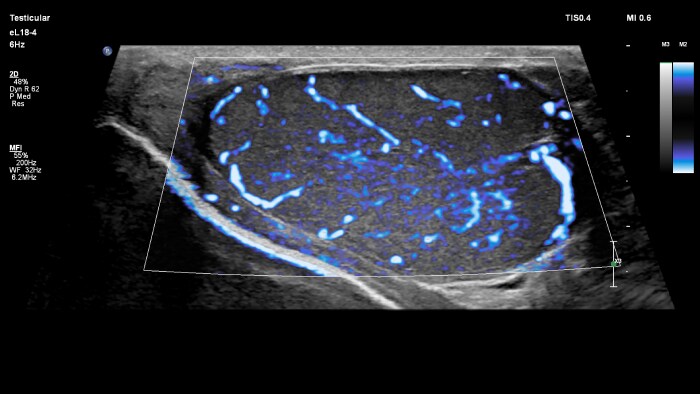

Small parts imaging is one of the fastest growing segments of ultrasound exams for clinicians around the world. Its wide array of applications includes assessing diseases and disorders of superficial organs like testicles and thyroid, as well as assessing musculoskeletal injuries like sprains and tears.

Image gallery